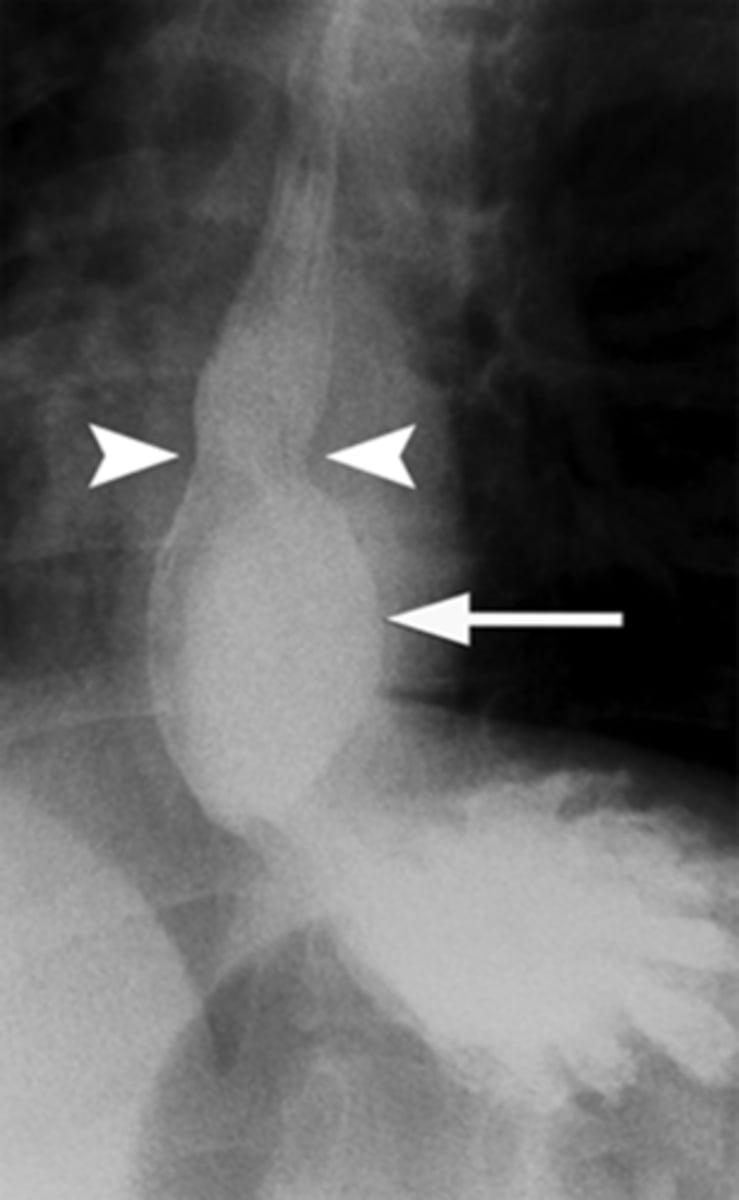

apple core lesion- colon CA